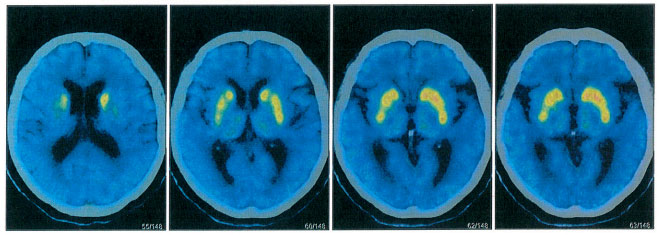

為了進一步鑒別診斷,張靜波主任團隊為患者進行了PET磁共振檢查(多巴胺轉(zhuǎn)運體、葡萄糖代謝、Aβ蛋白分子影像學鑒別),進一步鑒別帕金森病和老年癡呆。張靜波主任介紹,除了在惡性腫瘤的診斷、治療前評估與療效評估等應(yīng)用,PET在神經(jīng)系統(tǒng)疾病的診斷上也應(yīng)用廣泛。在腦顯像中,PET能提供病理生理學和分子水平信息,為神經(jīng)系統(tǒng)疾病(尤其是神經(jīng)退行性疾病和腦腫瘤等)的診療決策提供有力的證據(jù)。

PET影像結(jié)果示:腦部18F-AV45結(jié)果:雙側(cè)大腦半球皮質(zhì)Aβ(β-淀粉樣蛋白)未見異常沉積。腦部18F-FDG結(jié)果:雙側(cè)額葉、雙側(cè)尾狀核、中腦FDG代謝減低;雙側(cè)小腦FDG代謝減低。腦部11C- CFT結(jié)果:雙側(cè)尾狀核、雙側(cè)殼核前部、雙側(cè)殼核后部DAT(多巴胺轉(zhuǎn)運體)分布減低,右側(cè)明顯。

張靜波主任指出,如果是帕金森病,多巴胺轉(zhuǎn)運體是以進行性殼核損害為主,所以排除帕金森病。但是雙側(cè)大腦半球皮質(zhì)Aβ未見異常沉積,因此也排除老年癡呆。診斷方向進一步明確,張靜波主任進一步考慮為帕金森疊加綜合征。帕金森疊加綜合征是有帕金森病的綜合征的一些臨床表現(xiàn),但是伴有其他的一些神經(jīng)系統(tǒng)變性疾病的綜合征,比如說患者有可能有進行性核上性麻痹、皮質(zhì)基底節(jié)變性、多系統(tǒng)萎縮和額顳葉癡呆等疾病。最終,經(jīng)會診,確診額顳葉癡呆合并帕金森綜合征。